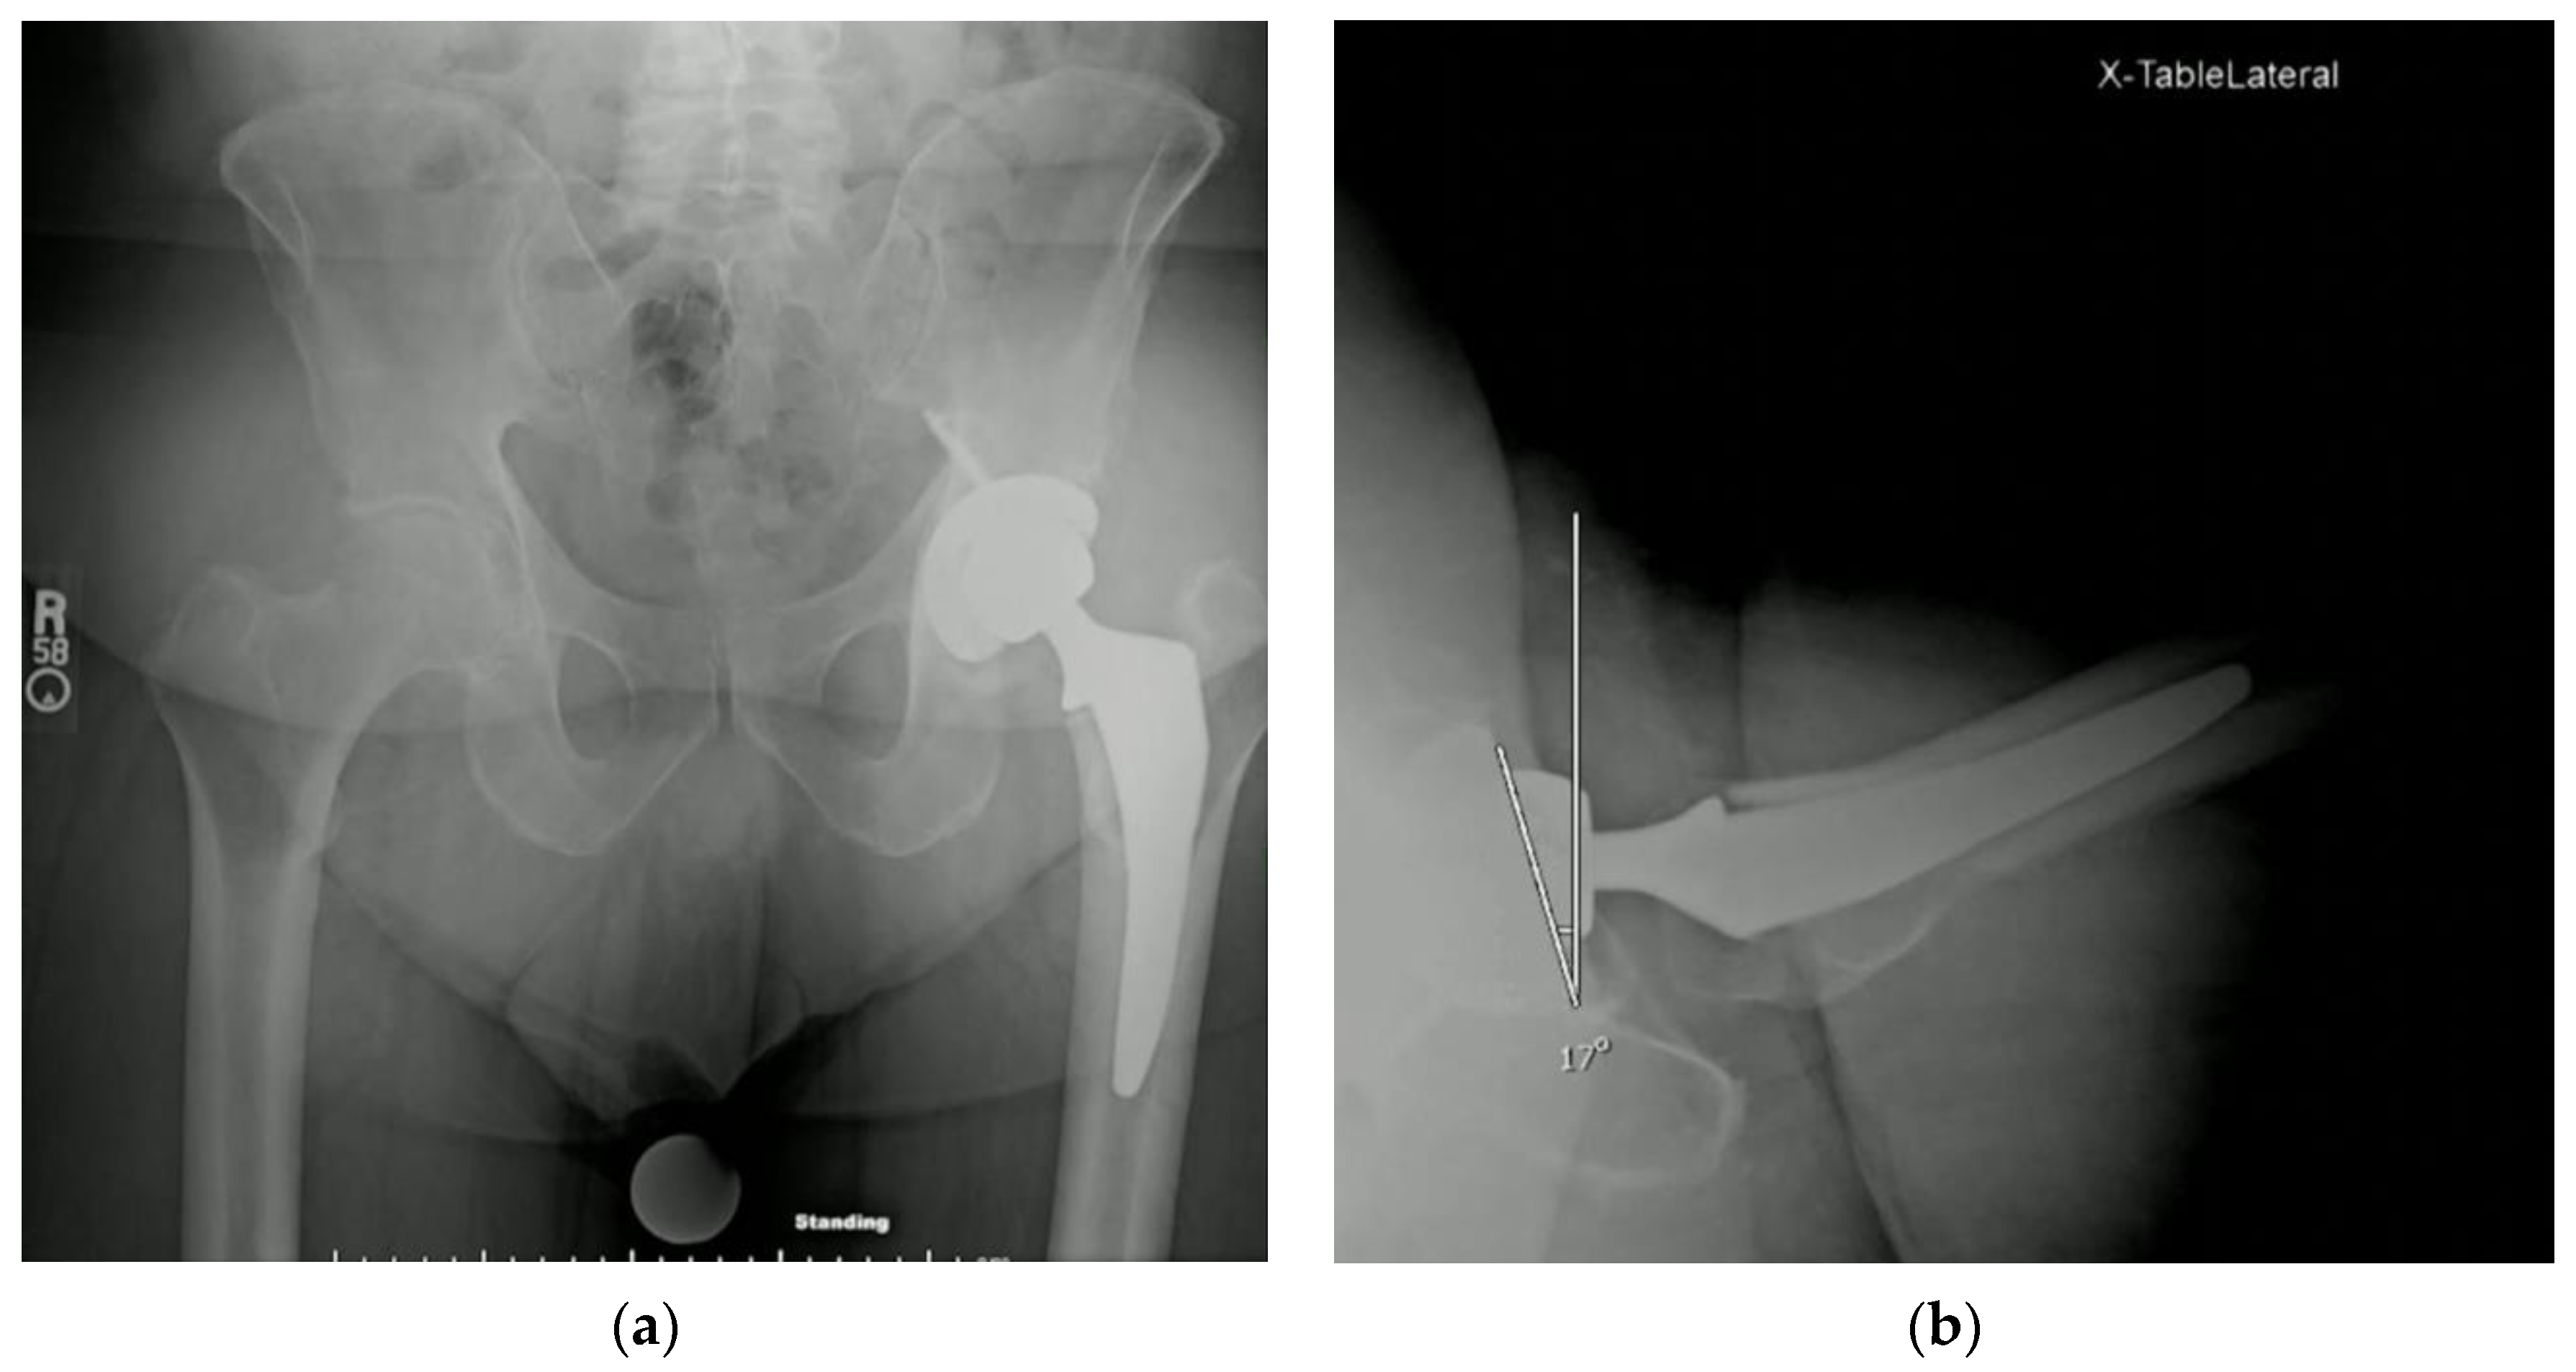

3.3. Protrusio Cases